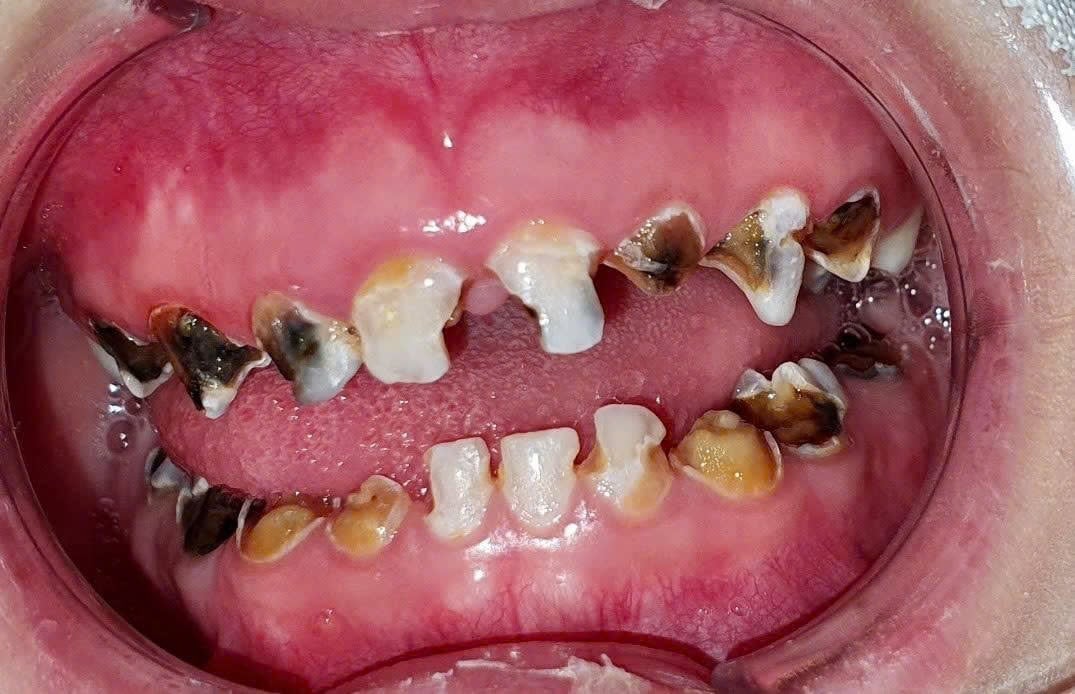

Bệnh nhân bị sâu răng cả hai hàm do vệ sinh răng miệng kém và không được điều trị sớm kịp thời. Ảnh: GS.TS. Võ Trương Như Ngọc.

Ở trẻ nhỏ, sâu răng sữa tiến triển nhanh và có thể gây viêm tủy răng, hoại tử tủy, suốt quá trình trẻ có thể không có cảm giác đau rõ rệt nhưng tủy răng bị hoại tử, viêm nhiễm lan đến phần quanh chóp tạo mủ, sẽ có mùi hôi đặc trưng. Ngoài ra, hôi miệng cũng có thể liên quan đến thói quen thở miệng, làm khô khoang miệng và tạo điều kiện cho vi khuẩn phát triển gây nên các bệnh lý viêm nhiễm đường hô hấp trên.